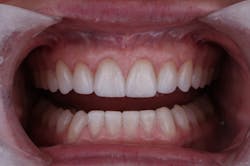

In this situation, we were able to achieve all of our functional and esthetics goals, which resulted in a happy patient (figures 22 and 23). The soft-tissue architecture was revised. The incisal edge positions and proportions were corrected. The shade, as well as the micro- and macro-esthetics, was improved. The exposed dentin and pulps of teeth Nos. 7–10 were covered and protected. Most importantly, we fulfilled the 5 requirements of occlusal stability for long-term functional success (figures 24 and 25).